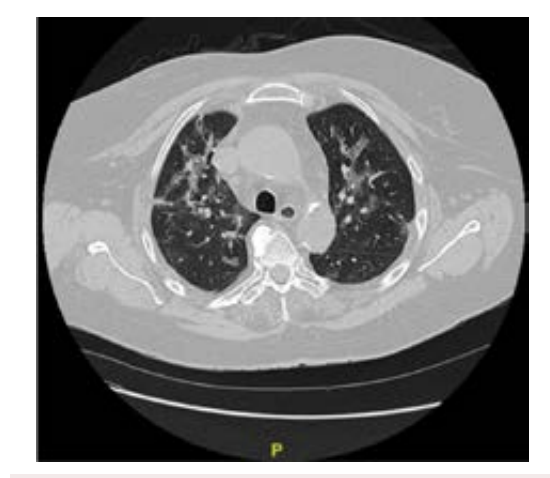

After intubation, the patient was diagnosed with refractory hypoxemia and succumbed to shock. Consequently, prone position was performed due to hypoxemia and the hypothesis of cor pulmonale was suggested due to the respiratory condition. Echocardiograms point of care (only apical window possible) showed enlargement of the right chambers with dysfunction of the right ventricle. It was decided to perform transesophageal echocardiography and it demonstrated a significant increase in the right chambers, without visualization of the proximal thrombus in the pulmonary artery; hyperdynamic left ventricular function and aorta without signs of ulcer or dissection, but large thrombus in ascending aorta (Figure 3).